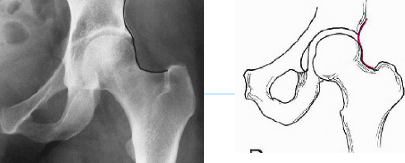

Q what is the name of this measurement? and what is the average + range?

A: Femoral Angle (Mikulicz’s Angle)

assesses the angle between the femoral shaft and neck. The normal range is 120-130°.

A: Skinner's Line

assesses the position of the femoral head relative to the greater trochanter.

Normal Finding: The fovea capitis should lie at or above the trochanteric line.

A: Klein's Line

assesses the alignment of the femoral neck and head, particularly for slipped capital femoral epiphysis (SCFE). No average or range is specified.